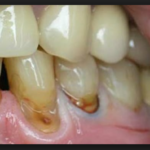

Кариес корня зуба фото

Кариес на корне зуба визуально практически никогда не определяется. Очень редко, и лишь в случаях, когда зубной камень значительно опустил ткани десны, может быть видно темное пятно или изъязвленный участок эмали. Чаще всего кариесом развивается на корнях передних нижних зубов и в межзубном промежутке. Во втором случае можно заметить снижение высоты десневого сосочка и увеличение межзубного промежутка в самой нижней его части.

Более того, кариес в большинстве случаев развивается по пути «наименьшего сопротивления» — зуб повреждается болезнью в направлении наиболее уязвимых участков. Поэтому кариес редко «поднимается» к коронке зуба, которая защищена толстым слоем эмали, и прогрессирует в направлении корня.